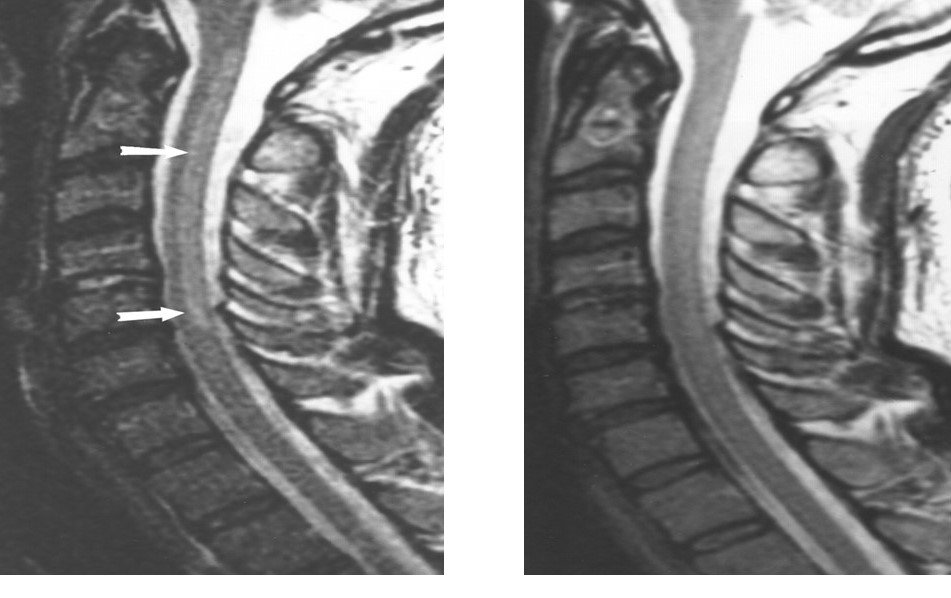

MRI of a patient with a spinal epidural abscess presenting with myelopathy. These abnormalities were initially missed when imaged without contrast and interpreted by general radiologists. (A) Sagittal T2 (fast spin echo) image demonstrating increased signal anterior to the cervical medullary junction at C1 and C2. (B) Sagittal T1 image with contrast, showing enhancement of the abscess, extending through the foramen magnum up to the clivus (arrow).